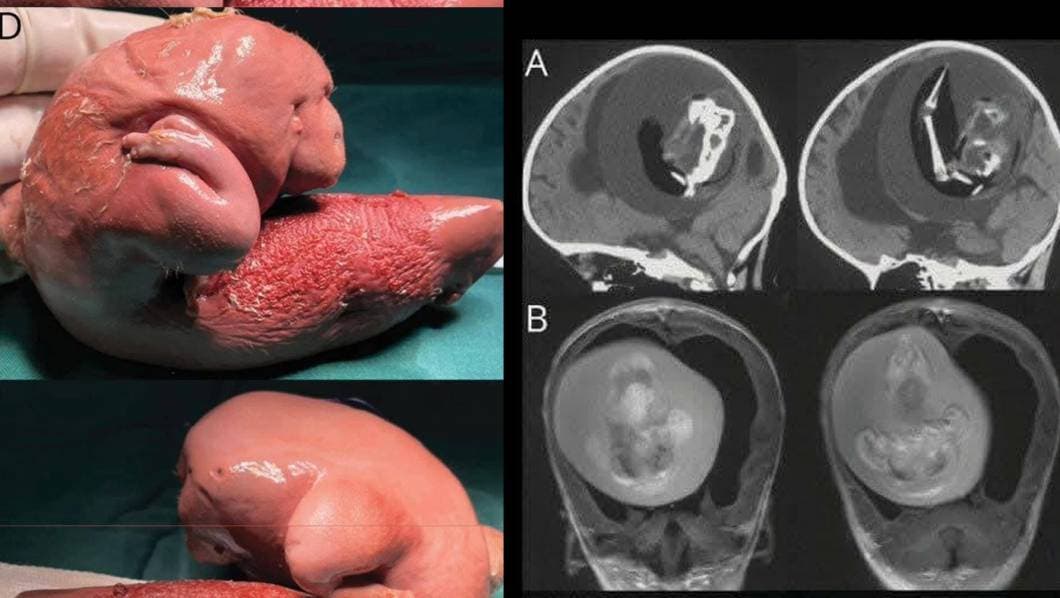

Un impactante y raro hallazgo médico ha dado la vuelta al mundo: una niña de apenas un año fue diagnosticada con un "fetus in fetu", una extraña condición en la que un gemelo malformado queda atrapado dentro del cuerpo de su hermano durante el embarazo. En este caso, los médicos descubrieron al “gemelo” alojado nada menos que en el cerebro de la menor.

El hallazgo se dio durante una serie de estudios rutinarios, cuando los médicos notaron una masa inusual en el cráneo de la pequeña. Tras realizar exámenes más avanzados, confirmaron la presencia del gemelo malformado, con estructuras bien formadas como huesos y tejidos. La niña fue atendida de inmediato y su evolución está siendo monitoreada por especialistas.

Fue descrito por primera vez en 1809, en la mayoría de los casos, la masa es no funcional, pero puede contener huesos, cabello o incluso órganos rudimentarios.

Aunque no siempre representa un peligro inmediato, puede causar complicaciones como infecciones, presión intracraneal o daño a órganos si no se detecta a tiempo.